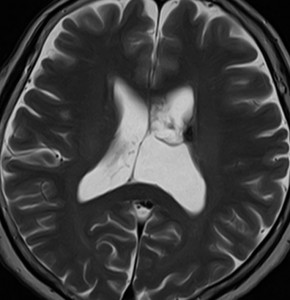

無症状の若い女性に偶然発見された例

central neurocytomaは腫瘍実質部分が多いものです。しかし,この例のように腫瘍の大部分をのう胞が占める症例もあります。

anterior transcallosal apprroachで亜全摘出しました。20代の女性でしたが,その後,子どもも生まれて元気です。

腫瘍の位置から,透明中核が発生母地であることが推測されます。central neurocytomaは,惻脳室壁にべとべとくっつくので,脳質上衣からの剥離は簡単ではありません。鑑別しなければならないのが,成人の毛様細胞性星細胞腫ですが,この症例では決定的な鑑別点はないでしょう。のう胞性の毛様細胞性星細胞腫と同様に,腫瘍の増殖力は低く無理して全摘出するものではありません。